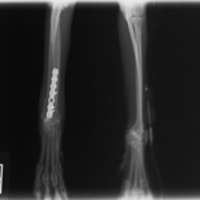

トイプードル 右遠位橈尺骨短斜骨折のALPSによる内固定

症例3:キルシュナーワイヤーのピンニングによる整復

ペルシャ猫 11ヶ月齢 雄

他院にて左大腿骨遠位の成長板骨折(salter-harrisⅠ型)が認められており、治療相談を目的として来院。当院にて、キルシュナーワイヤーを用いたピンニングにより骨折部位の整復を行いました。術後の経過は良好で、現在も経過観察中です。

術前レントゲン

術後レントゲン